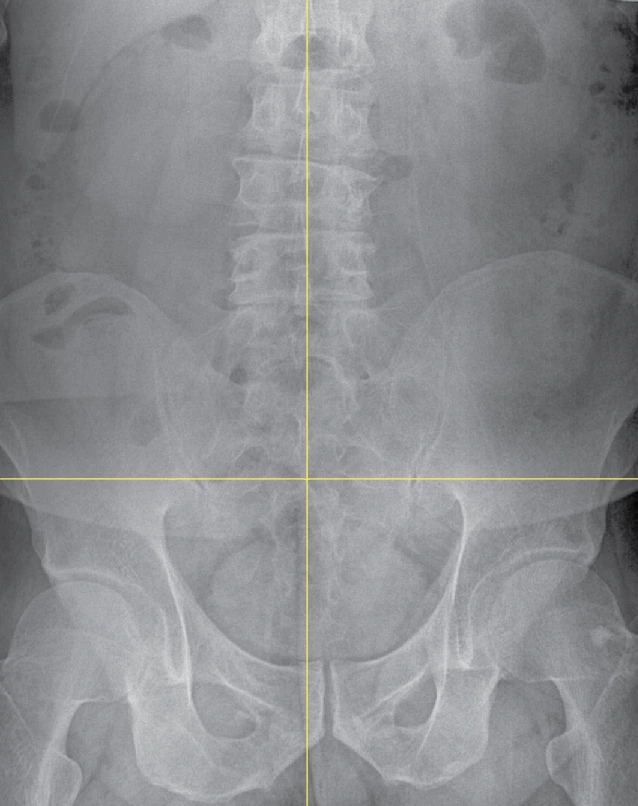

허리.PNG

따지자면 허리가 아닌 골반을 교정한 거다.

내 목은 일자목!

내 허리는 골반에서부터 틀어진 비정형 척추!

서프로는 내가 디스크라고 생각했던 허리를 골반 교정으로 바로잡았다. 거의 삼 개월 정도 된 지금 시점까지 오른쪽 발이 저리거나 한 적도 없었고 걷는 걸 두려워할 이유가 없어졌다. 이젠 다시 러닝을 시작해도 될 것 같다.